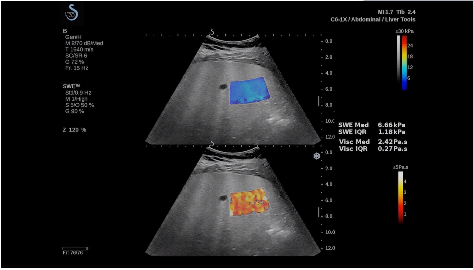

法國(guó)聲科影像(SuperSonic Imagine,SSI. Euroniex:FR0010526814)近日發(fā)表公告,宣布其研發(fā)的新一代“極速”超聲成像平臺(tái)(UltraFast Imaging),首次實(shí)現(xiàn)了肝臟的多項(xiàng)超聲定量評(píng)估新指標(biāo)同步檢測(cè),包括:Att PLUS,SSp PLUS和Vi PLUS等,基本涵蓋肝臟相關(guān)病理變化指征的如纖維化、脂肪變、炎癥等。據(jù)悉,此多項(xiàng)新技術(shù)新將搭載于新Aixplorer系列E超系統(tǒng)。

該公司首席執(zhí)行官(CEO)Michèle Lesieur女士介紹:“慢性肝病是危害公共健康的重要疾病,并呈逐年上升趨勢(shì)。目前,全世界約有8.44億人正在受到這種慢性疾病的折磨。2017年,我們已經(jīng)研發(fā)出了能夠有效輔助肝病臨床處理的部分早期診斷工具,這成為無(wú)創(chuàng)、準(zhǔn)確評(píng)估慢性肝病嚴(yán)重程度的里程碑之一。與眾不同的是,此次的全面化技術(shù)群,由于相關(guān)定量測(cè)量技術(shù)都是基于超聲可視化圖像為基礎(chǔ),因此有可能幫助臨床醫(yī)生更高效快速地完成日常診斷治療的完整流程”。

法國(guó)聲科影像公司(SuperSonic Imagine. SA,F(xiàn)rance),2005年由三位諾貝爾獎(jiǎng)級(jí)科學(xué)家主導(dǎo)創(chuàng)立,專(zhuān)注于E超的開(kāi)發(fā)和生產(chǎn),是目前世界上唯一可以同時(shí)應(yīng)用兩種波進(jìn)行人體檢測(cè)的系統(tǒng):縱波形成高質(zhì)量的二維組織結(jié)構(gòu)圖像,而橫波可以使醫(yī)生實(shí)時(shí)準(zhǔn)確地看到并分析組織的硬度,有效減少有創(chuàng)檢查、避免損傷。

E超相關(guān)技術(shù)已被多項(xiàng)多中心大樣本研究證實(shí)對(duì)于肝纖維化無(wú)創(chuàng)評(píng)估有重要意義,同時(shí)也可全面應(yīng)用于乳腺、甲狀腺、肝臟、前列腺、肌骨、婦科等全身各組織器官的定量評(píng)估和鑒別診斷。在慢性肝臟方面,聲科E超的肝臟相關(guān)定量診斷技術(shù)集,于2018年獲得美國(guó)FDA認(rèn)證,成為FDA歷史上首次獲批的單病種超聲全面定量解決方案。

E超是在原有B超、彩超(彩色多普勒CDFI)基礎(chǔ)上研發(fā)成功的新一代超聲剪切波彈性成像系統(tǒng),是一種能夠全面應(yīng)用于表淺組織、腹部臟器,血管等方面的組織彈性成像技術(shù)。根據(jù)組織硬度彈性值的不同,有效鑒別實(shí)性腫瘤的良惡性。對(duì)于惡性病變的診斷具有較高的特異性和敏感性,尤其對(duì)于甲狀腺、乳腺、前列腺等小器官,能夠完成常規(guī)超聲不能完成的組織定量分析,可以實(shí)時(shí)、全幅、全定量獲得組織彈性(硬度)信息,為鑒別腫瘤的良惡性提供客觀、量化的診斷依據(jù)。